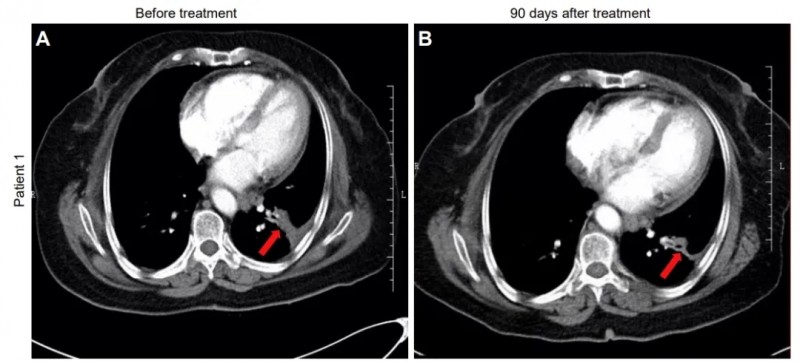

值得一提的是,A组2例典型患者,在治疗后均达到部分缓解(PR)。

患者1:是一位68岁女性,患IVA期非小细胞肺癌(NSCLC),治疗前左肺下叶可见3.8×1.8×2.4cm片状肿瘤;治疗90天后CT显示肿瘤缩小至2.5×1.2×2.1cm(详见下图)。

▲图源“JCI”,版权归原作者所有,如无意中侵犯了知识产权,请联系我们删除